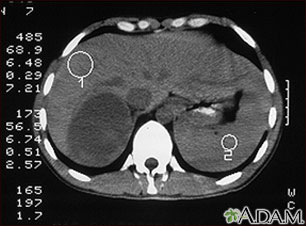

TC del abdomen superior de una persona con una masa en la glándula suprarrenal derecha. Las glándulas suprarrenales están situadas por encima de los riñones.